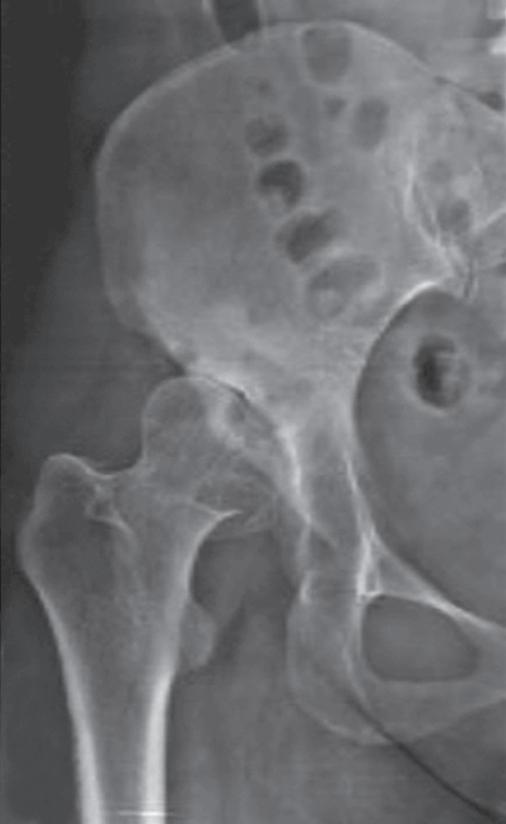

Com uma incidência de 2 a 4%, os distúrbios da maturação do quadril estão entre as malformações mais comuns do sistema musculoesquelético. A displasia do quadril é a causa mais comum de coxartrose precoce em todo o mundo, com a consequência da artroplastia precoce do quadril na idade do jovem adulto [18]. Para os afetados, a doença geralmente está associada a muito sofrimento ( ▶ Fig. 1.3).

Fig. 1.3 Consequências tardias de uma luxação do quadril.

a Coxa vara após necrose da cabeça femoral.

b Artrose na displasia do teto acetabular.

c Luxação inveterada do quadril.